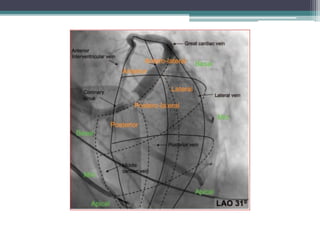

• Step 3: Defining the venous anatomy and

selecting a target vein

• Balloon occlusive retrograde coronary venous

angiography

▫ In AP, LAO 45 and RAO 30

▫ high-speed rotational angiography, over an arc

from RAO 55 to LAO55 for better definition of the

angle

 Acute takeoff angles of the CS tributaries (angles of

900 between the first-degree CS tributary and the

main CS) can impede cannulation.

Optimal site

• Optimal site may vary considerably for an

individual patient.

▫ In the majority of patients, preferred sites are

 Lateral

 Posterolateral,

 Non-apical position

 Non scar area

As far as possible from the RV pacing lead.

Segmental venous classification

• Thus 9 LV venous segments are derived which when added with the

conventional classification gives the best comprehensive information

to place the epicardial LV leads for CRT purposes